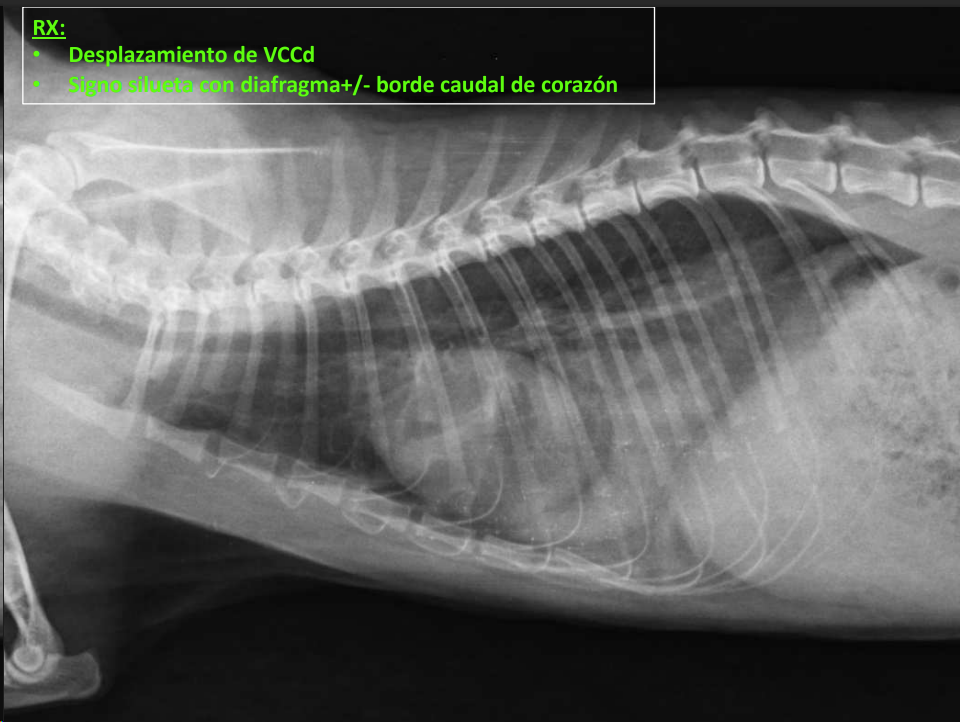

- Vena cava caudal: diámetro ≈ aorta.

- RX:

Efecto silhueta: cuando dos objetos de la misma densidad están en contacto, sus margenes no se pueden distinguir. No los distinguimos, los valoramos en grupo, buscamos cambios de tamaño, opacidad o de tamaño